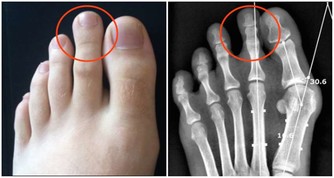

有些化學物質可能引起口腔癌、乳腺癌、神經疾病、心臟病、口腔潰瘍、牙齦損傷等疾病。